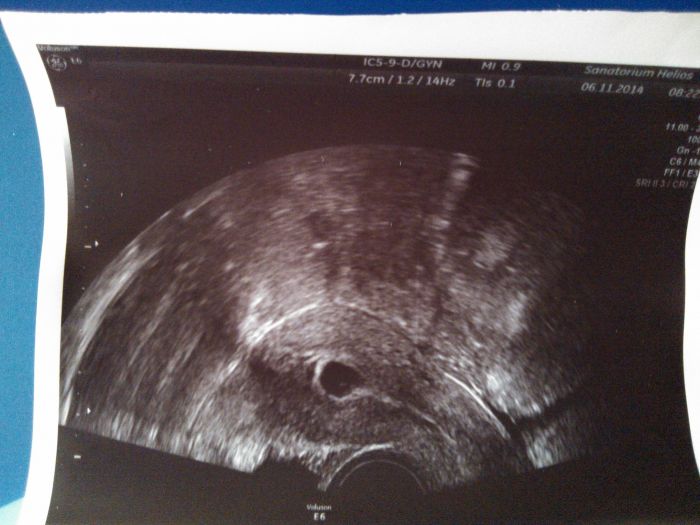

Ahoj holky, u mě taky tak, od dnešního rána krvácím, a měla jsem bolesti v podbříšku, ale už to ustoupilo a po krvácení není ani pamatky, a mimi tam normalně je......tak se držte, snad nam to všem dobře dopadne

[455659] Ahoj.Jsem v 6.tydnu nejdriv jsem zacla spinit hnedy vytok. Tak jsem si zasla do nemocnice a tam mi nasly vaces o vel.3,7mm ale zadne embryo.Dnes jsem zacla krvacet tak sem zasla do nemocnice a tam mi rekly ze vacek je uz 1cm veliky a v nem embryo.Ptala jsem se ohledne toho krvaceni a rekl mi ze muzu krvacet 1.den nebo tyden nebo i 6.tydnu.V pondeli jdu nakontrolu.Ale porad krvacim tak se bojim ale i doufam ze bude vse v poradku.